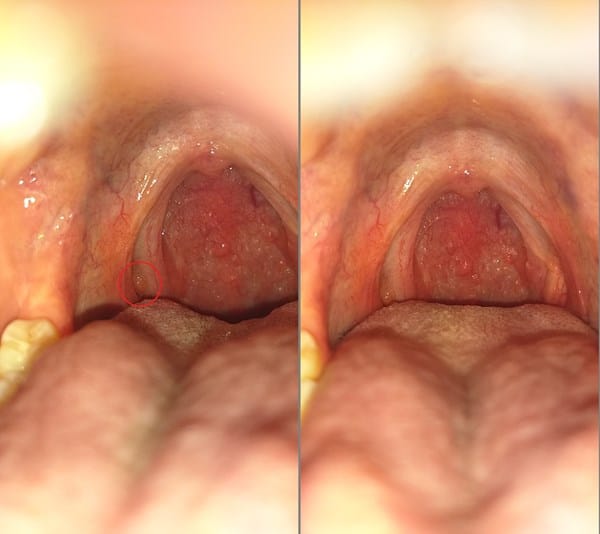

Desde hace un mes siento que tengo algo atorado en la garganta únicamente cuando trago saliva. Me revise y tome una fotografía y note esa protuberancia que se ve encerrada en rojo. El medico me diagnostico faringitis y receto claribiotic 500 (claritromicina) hace 2 días pero no se me va. No levante temperatura ni tos, algunas veces flemas en la faringe pero solo eso. ¿Estará bien el diagnostico o es un papiloma?